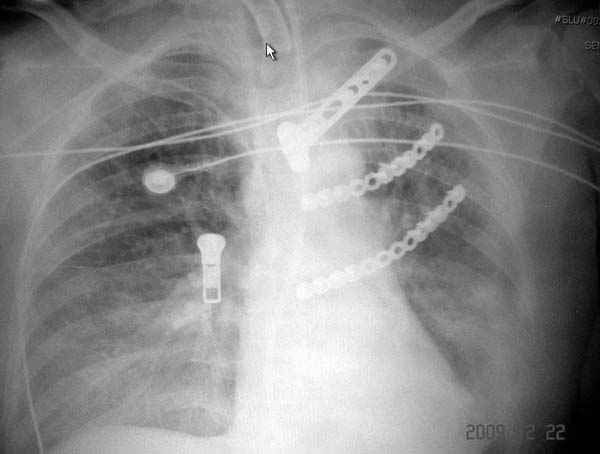

На седьмые сутки нами совместно с торакальным хирургом сделана операция по фиксации грудинно-ключичного сочленения и переломов ребер.

После кожного разреза обнаружили полный разрыв грудной мышцы и повреждение перикард от уровня второго до восьмого ребер. Хирург находился с нами и после нашей работы зафиксировал повреждение перикарда и разрыв грудной мышцы.

Не все переломы ребра фиксированы, и поэтому хотели услышать комментарии тех, у кого имеется опыт.

Пластина из Synthes http://int.synthesmatrixrib.com/html/Overview.5.0.html